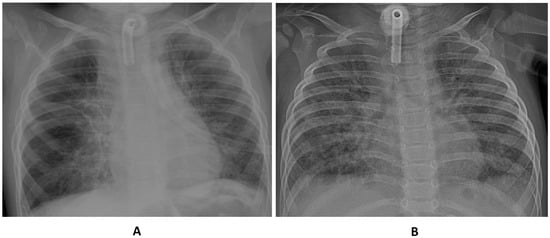

3.2. Respiratory Condition

- Mechri, M.; Epaud, R.; Emond, S.; Coulomb, A.; Jaubert, F.; Tarrant, A.; Feldmann, D.; Flamein, F.; Clement, A.; de Blic, J.; et al. Surfactant protein C gene (SFTPC) mutation-associated lung disease: High-resolution computed tomography (HRCT) findings and its relation to histological analysis. Pediatr. Pulmonol. 2010, 45, 1021–1029. [Google Scholar] [CrossRef] [PubMed]